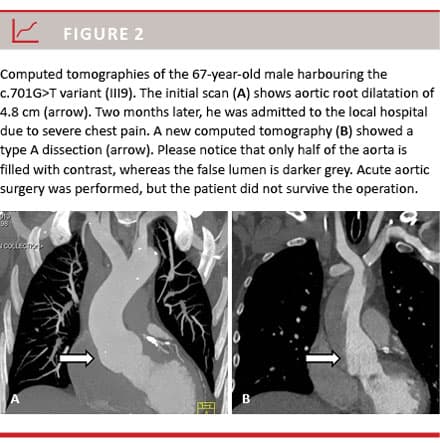

A 67-year-old male family member with the c.701G>T variant (III9) was found to have aortic dilatation of 4.8 cm (Figure 2A). He was offered preventive aortic root surgery, but died from a fatal aortic dissection shortly before the planned operation (Figure 2B).